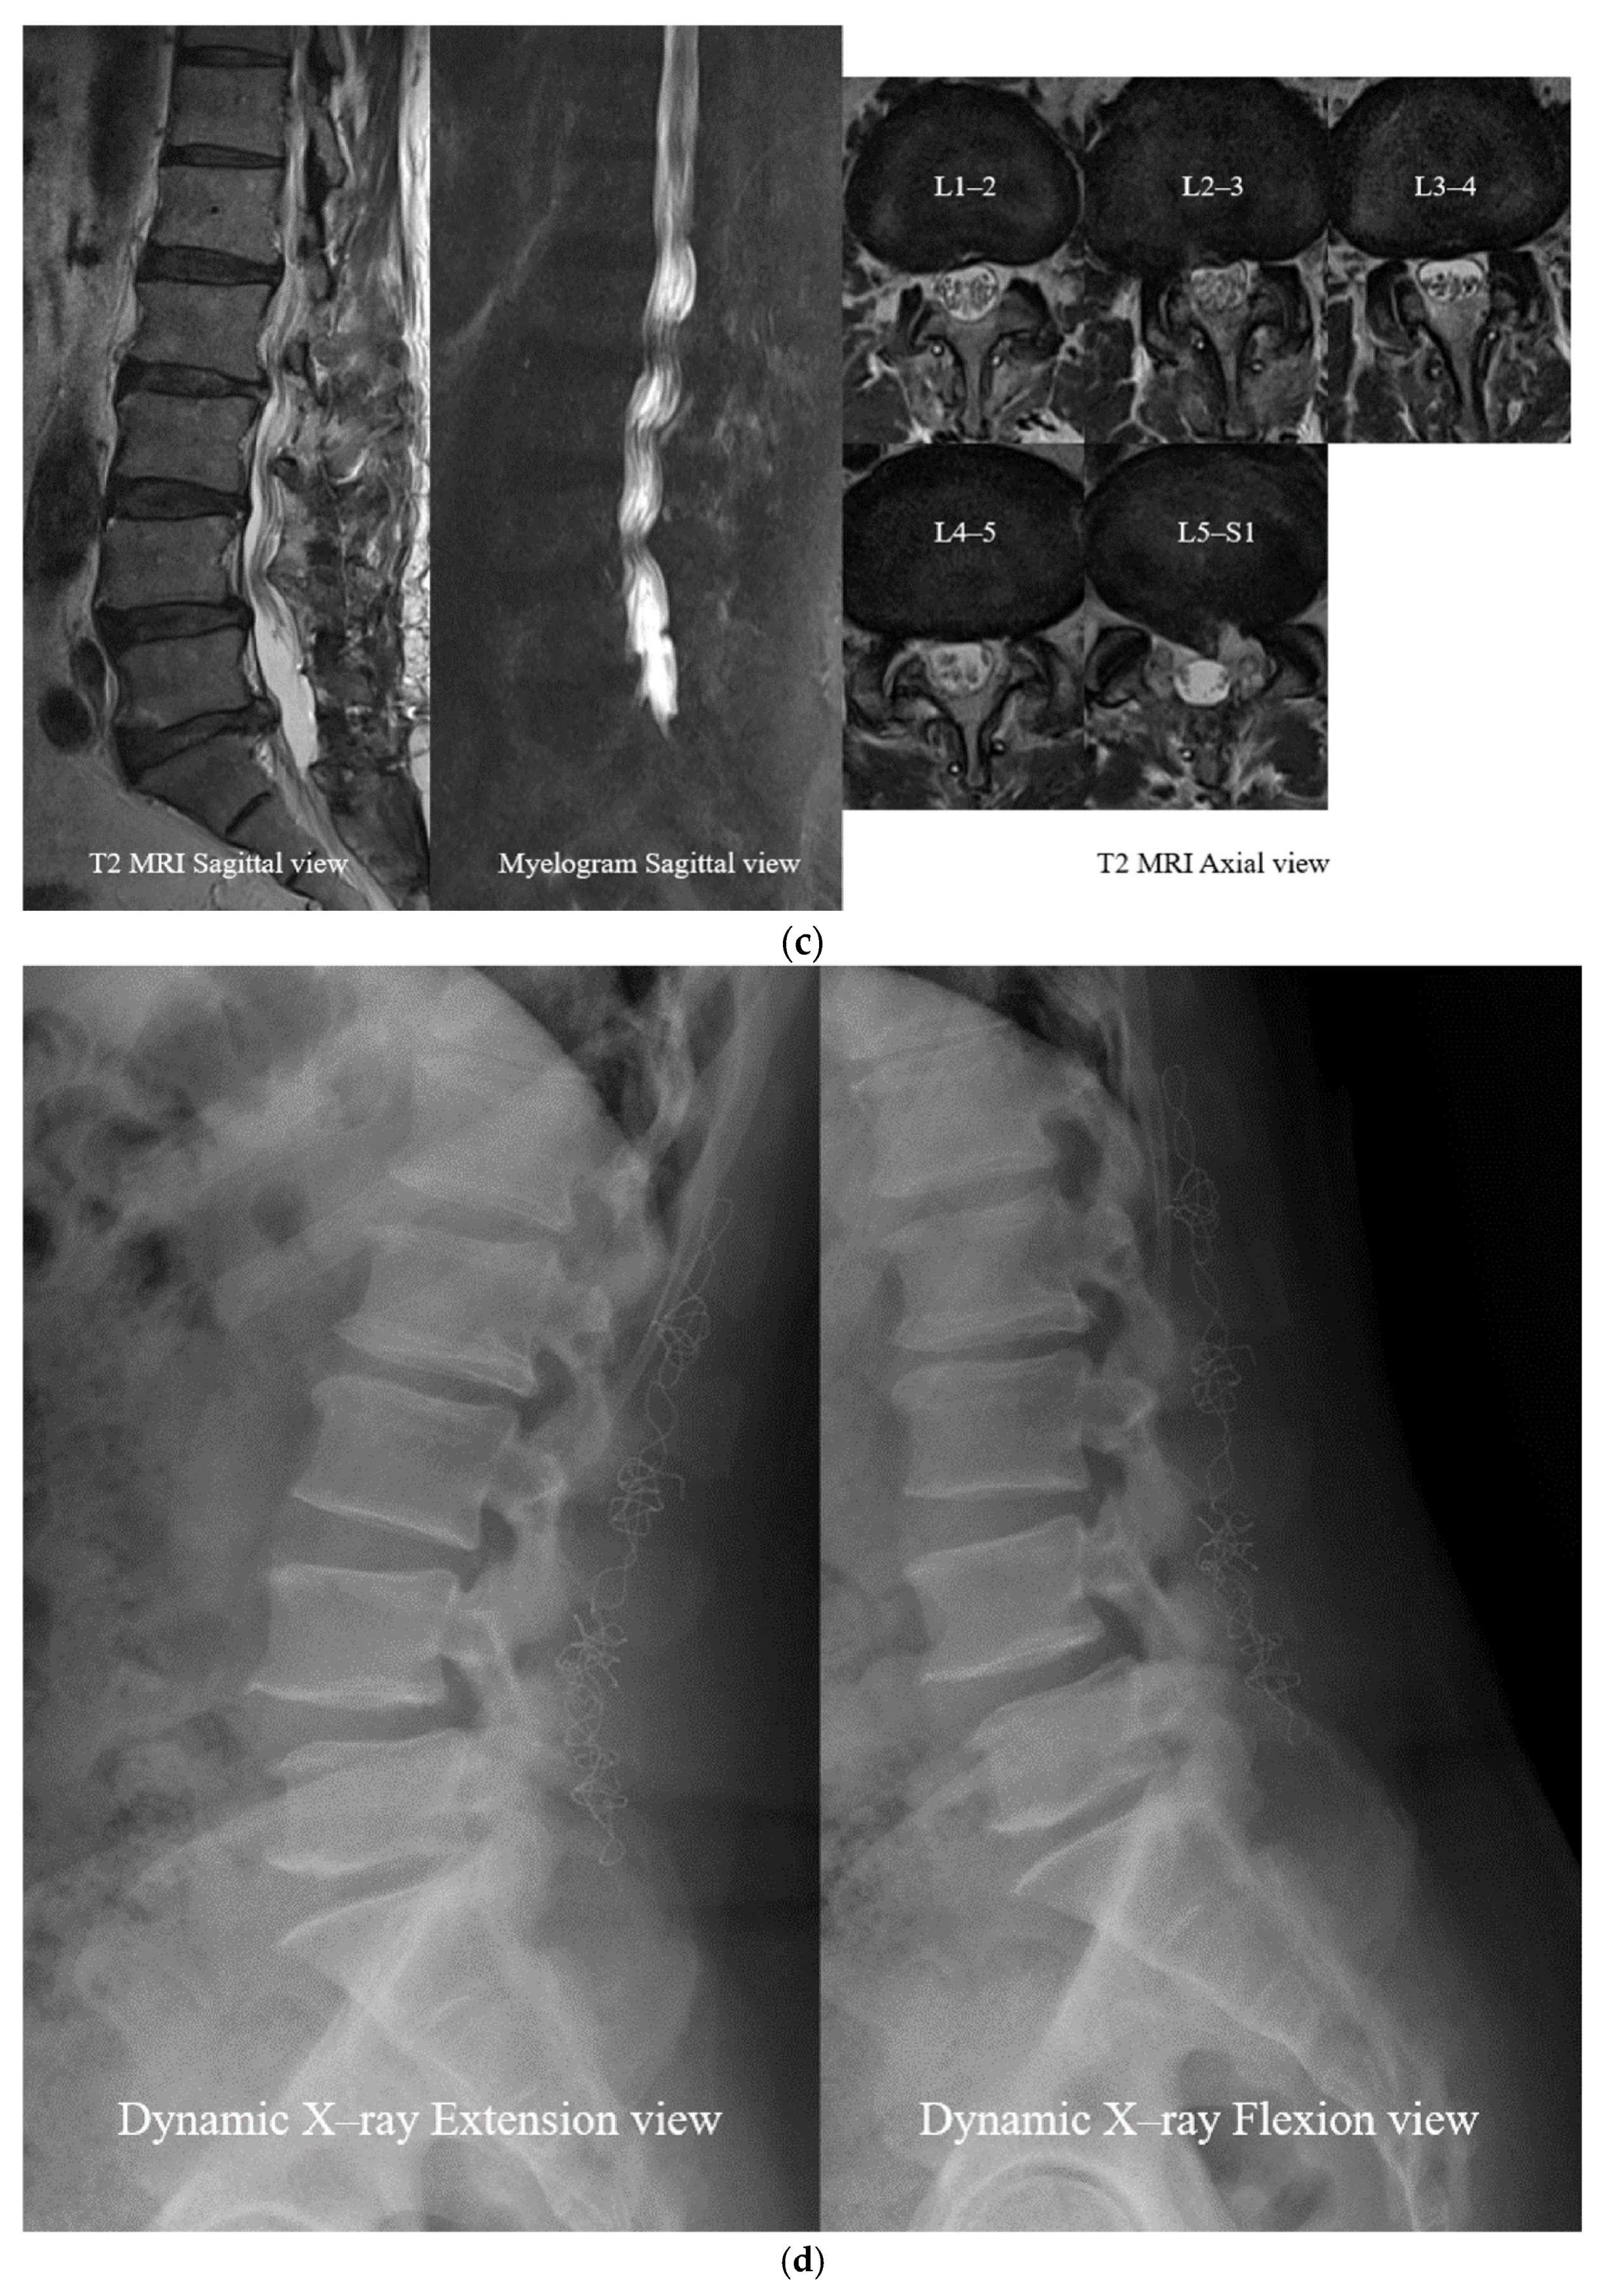

- Open Midline Decompression

- Ligament Reconstruction